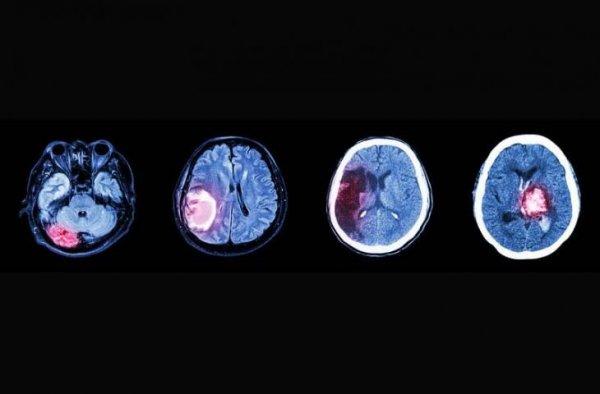

Ependimom; kistik olmayan beyin veya omurilik içindeki hücrelerin kontrolden çıkmaları sonucunda meydana gelir.

Doğrudan sinir sisteminden kaynaklandığı için MSS (Merkezi sinir sistemi) tümörleri olarak adlandırılırlar. Bazı tümörler hızlı, bazıları ise yavaş yayılır.

EPENDİM HÜCRELERİNDEN KAYNAKLANIR

Ependimom kontrolden çıkan ve değişen, kötü huylu hale gelen ependim hücrelerinden kaynaklanır. Ependim hücreleri beyin odacıklarının (beyin ventrikülü) ve omurilik kanalının (spinal kanal) iç duvarlarını kaplamaktadır.